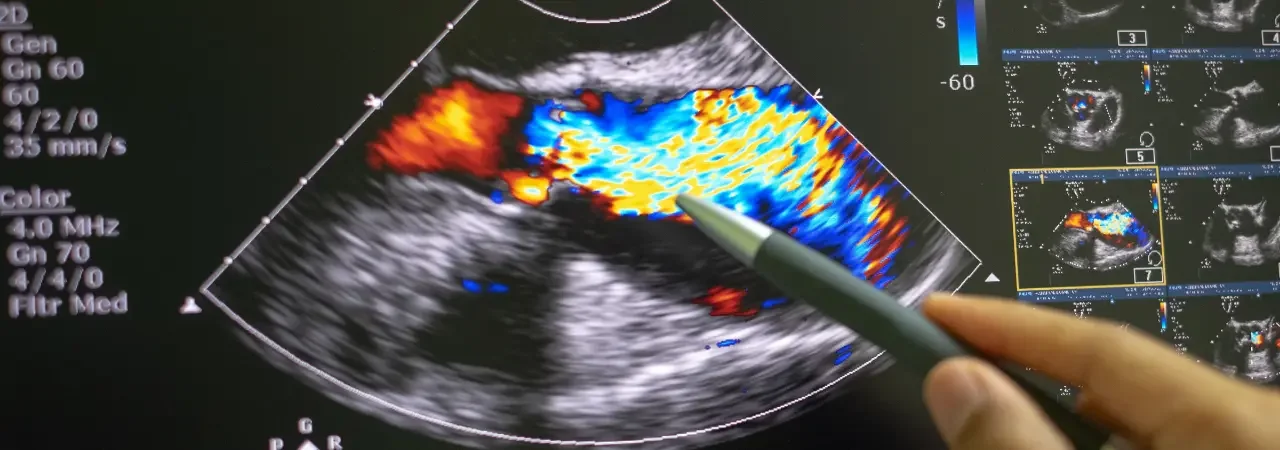

- Ekokardiyografi ile biküspid kapak, kök genişlemesi ve ventrikül fonksiyonunu değerlendiririz.